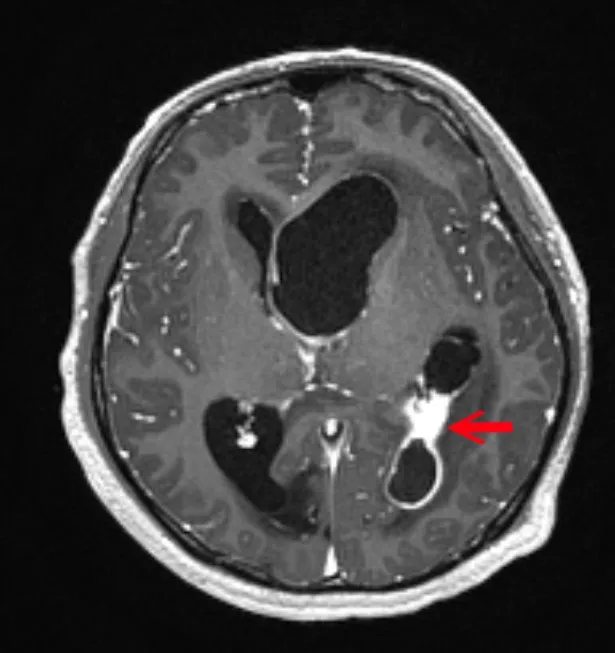

MRI顯影個案阿成的左腦腦膿瘍位置(白色範圍),水腦會造成對側運動功能受損,由於左腦主管語言,口說理解能力亦會受影響。中國附醫提供

中國醫大附醫專家團隊評估阿成腦內無故長膿,疑與先天性心臟疾病相關,經照會中國附醫兒童醫院兒童心臟科醫師戴以信後續診斷,以「氣泡測試超音波檢查(Bubble test, Agitated Saline Echocardiography)」以及心導管檢查阿成的心臟,發現「心房中隔缺損(Atrial Septal Defect)合併右到左分流」導致他長期慢性缺氧,因右心房的缺氧血逆流進左心房,細菌進而大舉侵入腦部,造成嚴重感染膿瘍再併發水腦,幸好阿成被即時搶救,兒童醫院心臟團隊接續使用「經心導管心房中隔關閉手術」,關閉阿成心臟的先天破洞,防止腦部膿瘍再次發生,術後恢復良好,阿成目前持續復健中。